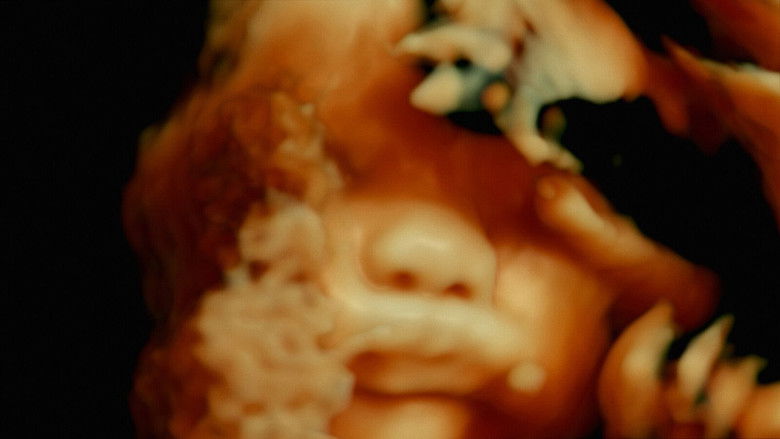

De humani corporis fabrica  документальный

Необыкновенное приключение по внутренностям человеческого тела; или открытие инопланетного ландшафта невиданной красоты.